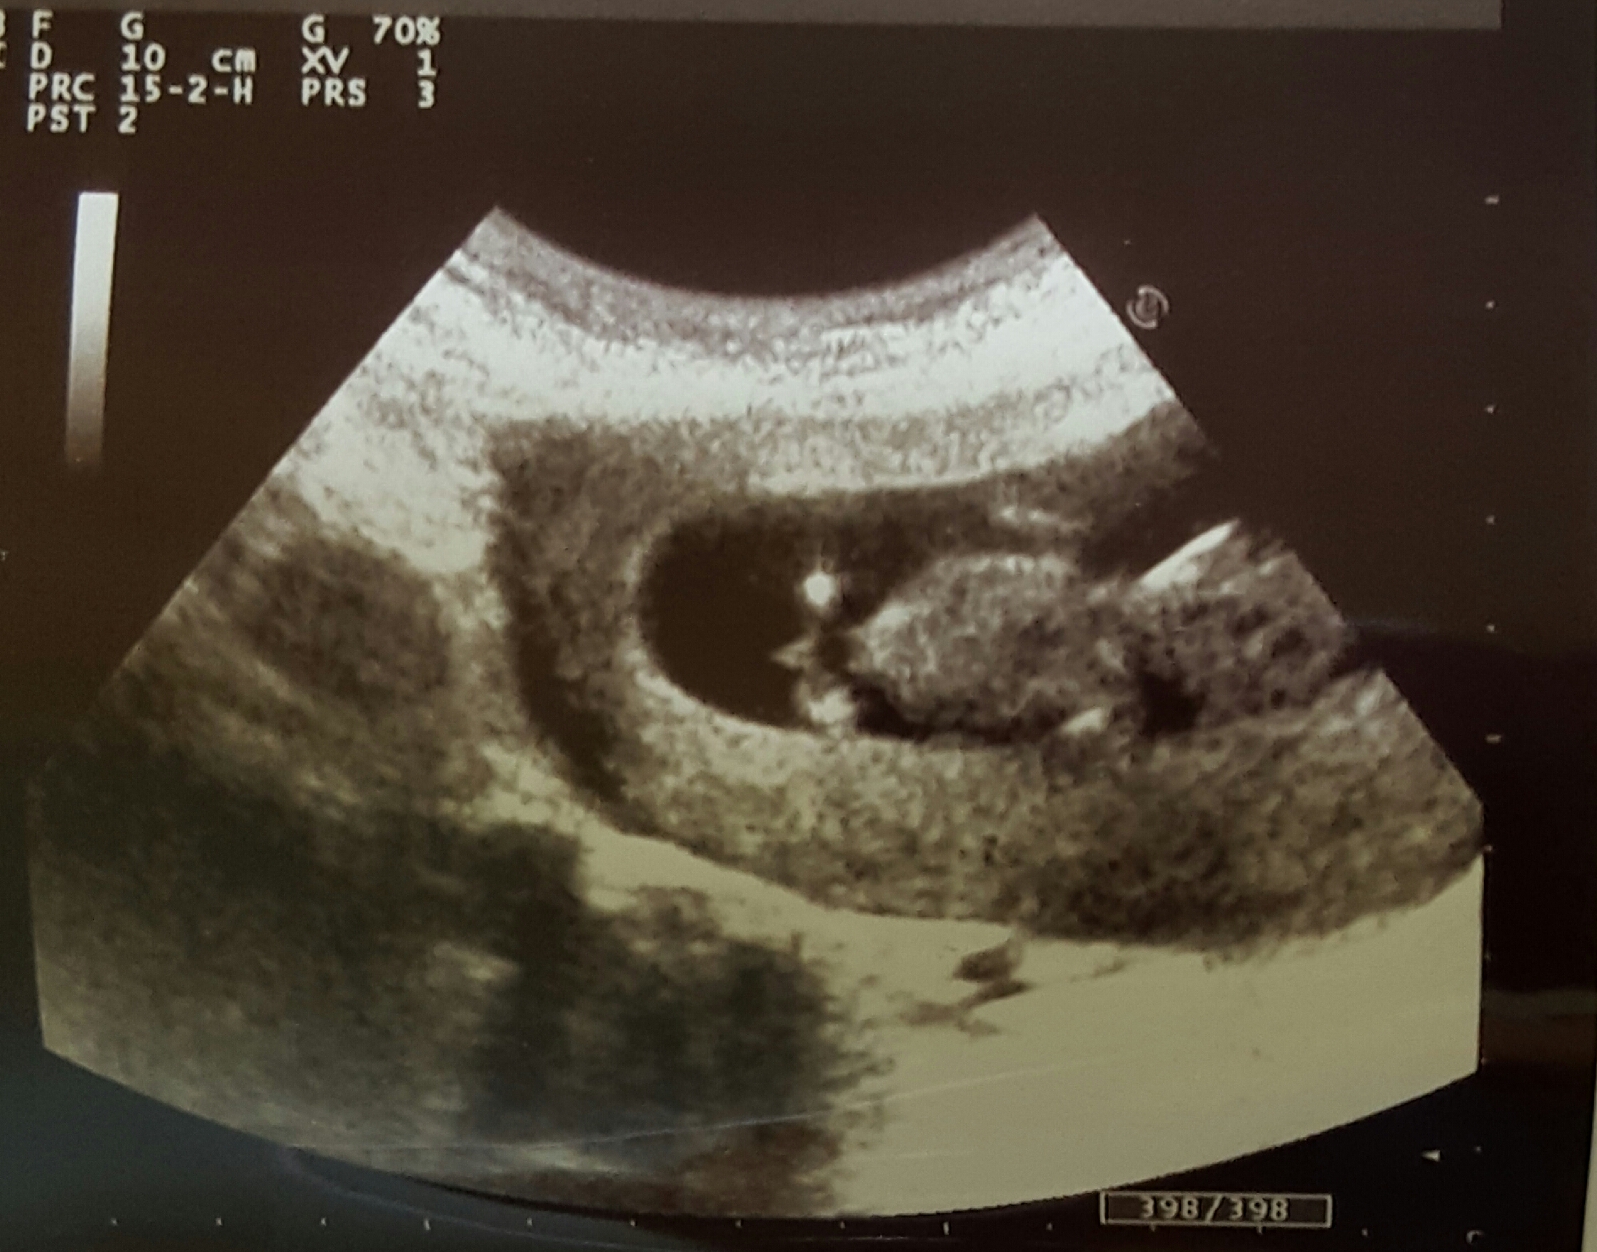

Anyway, I have a question about potty shots. I got this shot at 11 weeks 4 days but was measuring 12 weeks 4 days

..so I am not even sure what week it wud really be.

I most definitely see something like a penis there lol but the doctor was saying that at this stage it could just be the lower spine?

What do you guys think? And can anyone shed light on why potty shots aren't generally used at this stage, even if it seems so obvious that it's a boy?

Attachment 28545